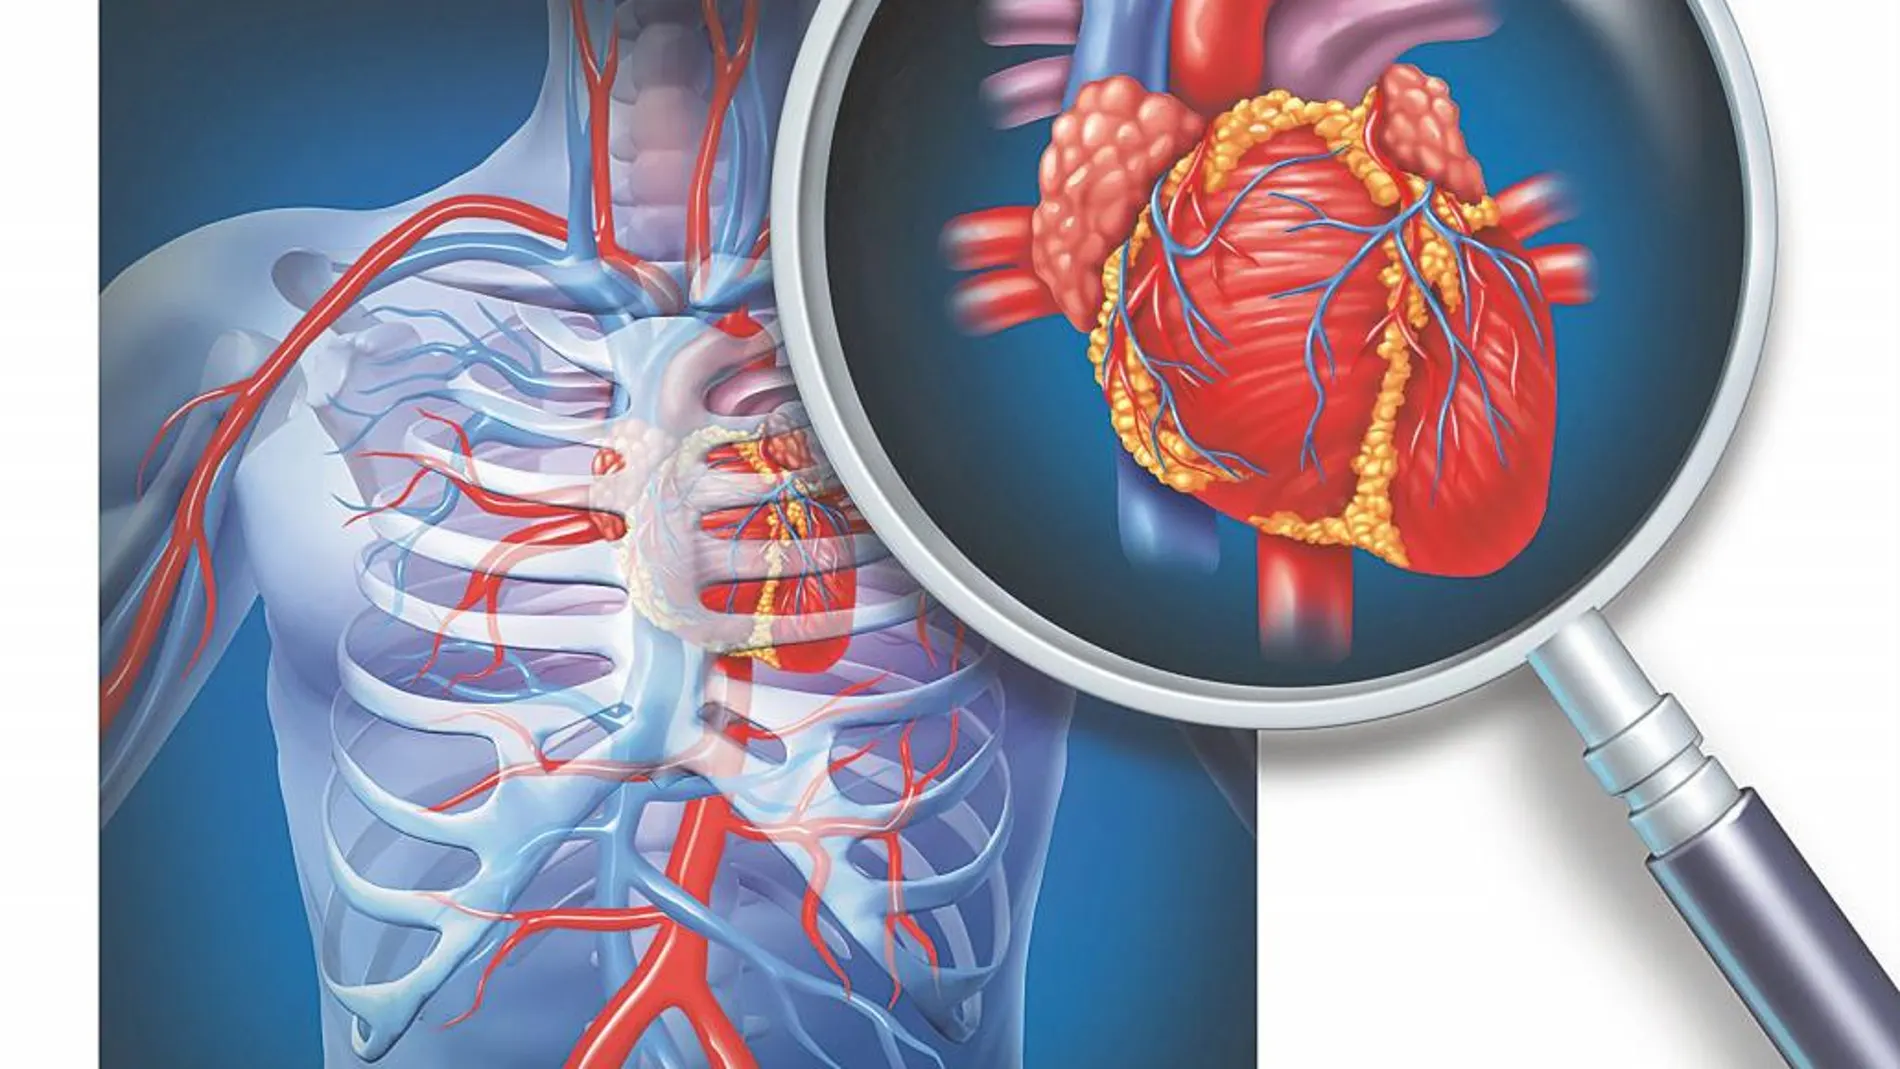

Es eficaz, altamente sensible, segura, indolora y permite, incluso, aventurar si se puede llegar a producir un evento cardiaco: un infarto. Hablamos del «mejor detective» de la salud de las arterias del corazón, la llamada cardiología nuclear. Llegó a España hace ya más de cuatro décadas y gracias a sus avances forma parte imprescindible de los servicios de cardiología de los centros médicos de referencia de nuestro país.

Antonio Álvarez Vieitez, del Servicio de cardiología del Hospital La Milagrosa de Madrid, aclara: «la cardiología Nuclear ha desempeñado un papel trascendental en el desarrollo de la medicina nuclear en los últimos 25 años. Se trata de una subespecialidad de la cardiología y de la medicina nuclear que permite, mediante la inyección de dosis bajas de compuestos radiactivos (el Tecnecio 99 es actualmente el más utilizado y no es nocivo para para el paciente) capturar imágenes ‘in situ’ de la fusión cardiaca en reposo o en movimiento. Todo gracias al uso de una gammacámara».

También denominada cámara de gammagrafía, detecta la energía radioactiva que es emitida desde el cuerpo del paciente, y la convierte en una imagen. La gammacámara no emite ningún tipo de radiación. «El paciente no está ‘‘enclaustrado’’ como en otras pruebas como la Resonancia Magnética (RM) o el escáner (TAC), sino que es abierta. Tiene la forma de ‘‘donut’’ redonda circular que tan solo se sitúa en la caja torácica del paciente, donde allí puede medir el flujo de la sangre que, a través de las arterias coronarias, llega al corazón y también su contractilidad», recalca el doctor Álvarez Vieitez.

Funcionamiento

Se inyecta en una vena periférica, mientras el paciente está tumbado y en reposo. En ese momento se puede observar cómo funciona su corazón. Posteriormente, se le somete a una prueba de esfuerzo o a un electrocardiograma. Así podemos obtener imágenes del corazón mientras el paciente descansa e inmediatamente después de hacer ejercicio. Con este estudio «es posible averiguar el tamaño de las cavidades cardiacas, cómo bombea el corazón la sangre y si hay músculo cardiaco dañado o muerto. En el caso de pacientes que estén invalidados para hacer la prueba de esfuerzo lo que hacemos es inducir el mismo efecto de esfuerzo pero con fármacos», apostilla el experto del Hospital La Milagrosa. Los «perfectos candidatos a esta prueba son pacientes con dolor de pecho injustificado o que se presenta al realizar ejercicio (denominado angina); o los casos en los que el especialista quiere determinar la forma y función (contracción) del corazón; la irrigación sanguínea al músculo cardiaco por las arterias coronarias, aportar información sobre el pronóstico de la patología o establecer la respuesta al tratamiento (bien sea con fármacos o tras una cirugía)», añade el experto.

«La mayoría de los cerca de 50 pacientes que mensualmente se someten a la prueba en nuestro servicio tiene más de 50 años y son tanto hombres como mujeres. Si el estudio muestra que el flujo sanguíneo es normal mientras descansa pero no cuando hace ejercicio, entonces sabemos que el flujo no es adecuado y estamos ante un caso de isquemia. El corazón normalmente bombea más sangre en momentos de esfuerzo físico. Si los resultados del estudio son anormales durante ambas fases (reposo y ejercicio), el corazón tiene una zona cicatrizada o permanentemente privada de sangre, lo que consideramos una oclusión. Cuando no podemos observar la sustancia radiactiva en una parte del corazón, probablemente signifique que ha muerto esa sección del músculo cardíaco, ya sea debido a un ataque cardíaco previo o porque están obstruidas las arterias coronarias que riegan esa zona del corazón», explica el experto. Toda esta información, obtenida en menos de una hora y sin riesgos para el paciente, es crucial para determinar su salud cardiaca de forma preventiva y predictiva.